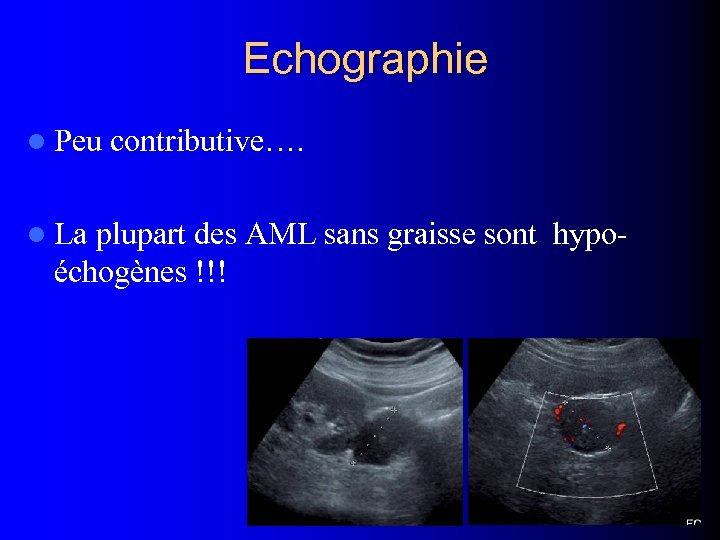

Echographie l Peu l La contributive…. plupart des AML sans graisse sont hypoéchogènes !!!

Echographie l Peu l La contributive…. plupart des AML sans graisse sont hypoéchogènes !!!